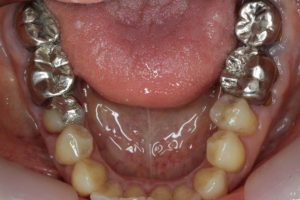

- 術前

- 術後

長い間お疲れさまでした。この方は、前歯に審美的なインプラントを入れるため、抜歯後4ヶ月待ち、仮歯で歯肉が成熟するのを数が月待っていたりした為に、完成まで時間がかかってしまいました。

虫歯治療などは短期間で終えることができるのですが、歯ぐきをいじり出すとどうしても治癒期間が必要となり長くなってしまいます。それもこれも奇麗な仕上がりのために欠くことのできないものです。何卒ご容赦を!